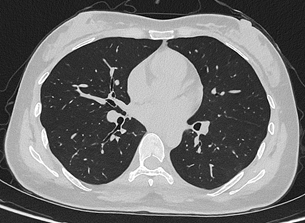

目前,华西厦门医院已基于该设备完成第一批患者扫描。华西厦门医院党委书记廖志林表示,光子计数能谱CT的临床落地实现了对国外“卡脖子”技术的突破,大幅降低了辐射剂量,让患者CT扫描更安全。临床案例显示,设备在低剂量条件下仍可实现肺结节的高清成像,临床价值突出。该设备将在医院的全链条、全生命周期健康管理服务中发挥重要作用。

联影uCT Ultima扫描的0.2mm肺部超高清成像,扫描剂量低至0.1mSv